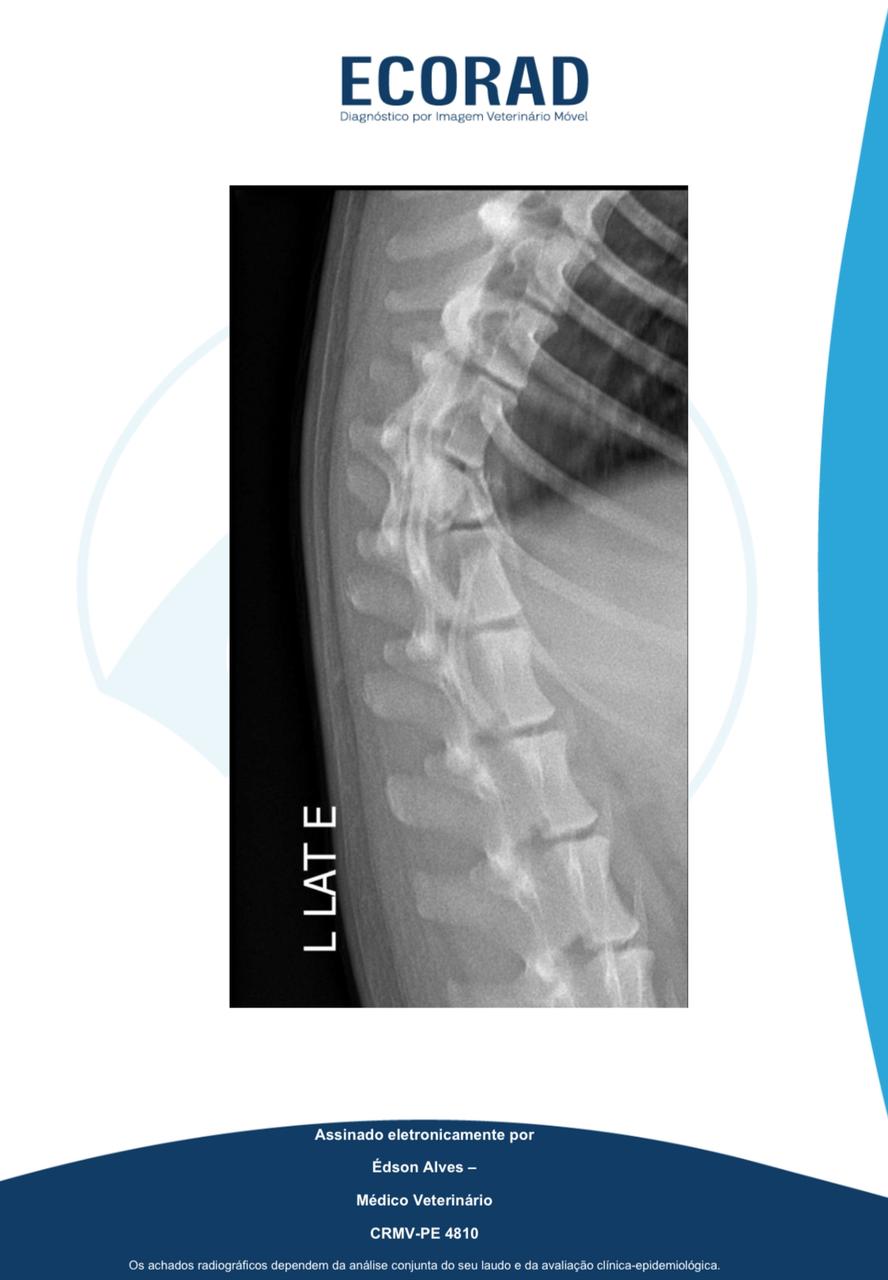

A situação aconteceu no Viaduto da Caxangá, na Iputinga, Zona Oeste da capital pernambucana. Com a queda, o animal fraturou a coluna.